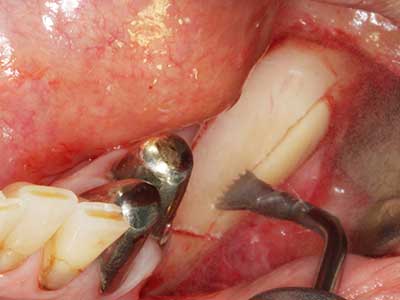

When surgical procedures are performed on bone in the immediate vicinity of sensitive structures such as blood vessels or nerves, rotary instruments pose a significant risk of iatrogenic injury. Piezoelectric devices can be helpful for preparation of bone covers and removal of hard tissue close to nerves, particularly for exposure of nerves after iatrogenic injury but also during nerve lateralization for resective and reconstructive procedures or implant placement (Fig. 17-20). Light contact between the piezotip and the nerve does not generally result in damage but proceeding incautiously with saw-like motions or attachments where a residual bone substrate remains may cause temporary or even permanent nerve damage. However, the risk of damage is considered to be substantially lower than when using saws or milling instruments (Pereira, Gealh et al. 2014).

Fig. 18: Preparation of a cortical cover with the piezo bone saw (Piezomed, W&H).

Fig. 19: Surgical site after neurolysis and removal of osteoma.

Fig. 20: The removed bone cover is re-adapted and fixed with an osteosynthesis screw (KLS Martin, Tuttlingen).